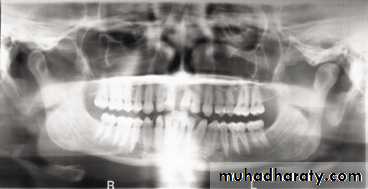

A dental panoramic tomograph showing the main real soft tissue and air shadows drawn in on

one side of the radiograph, NC — nasal cartilages, EL — ear lobe, SP — soft palate,DT — dorsum of tongue, Or — oropharnyx, NF — naso-labial fold, M — mouth.